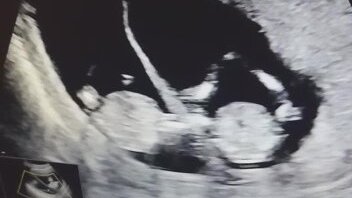

Существует такая теория, что по одному из параметров результатов УЗИ можно определить пол ребенка. Конечно, оборудование уже позволяет определять пол на первом скрининге и без всяких гаданий и теорий, но это зависит от уровня технической оснащенности конкретного медицинского заведения, квалификации специалиста и...конечно же от настроения самого специалиста! Мы живем в России, не забывайте. У меня два ребенка. Первый скрининг для меня каждый раз был огромным испытанием после неудачной первой ЗБ, с которой и до скрининга дело не дошло...

Всем доброго времени суток! Открываю новую рубрику ответы на самые часто задаваемые вопросы от пациенток. Что входит в первый скрининг? Это исследование состоит из двух частей: ультразвуковой диагностики и оценки некоторых параметров крови. На основании результатов выявляют вероятность!!! генетических заболеваний плода, риски осложнений протекания беременности. Важно, что диагнозы не ставят, а только считают возможные риски. На основании результатов ваш лечащий доктор может заподозрить отклонения и проведет углубленную диагностику...